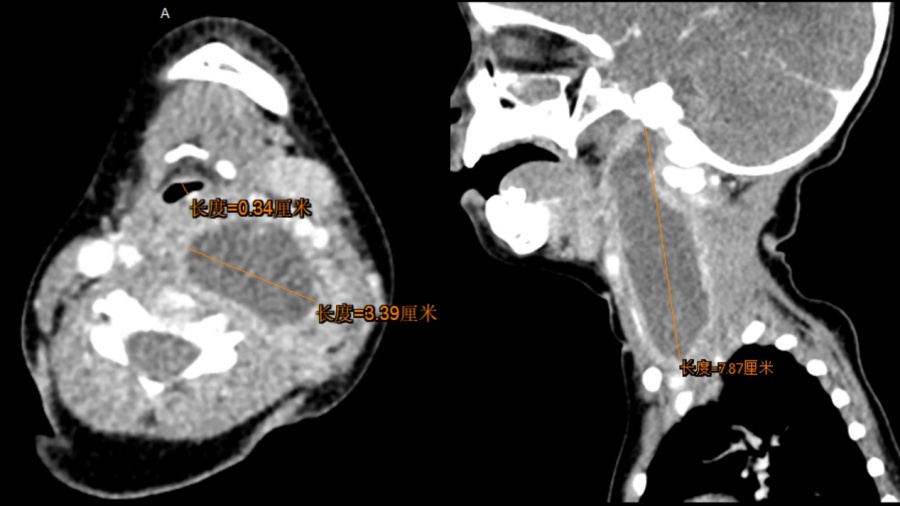

接到急诊前台来电后,医院耳鼻喉科当班二值和住院总医师立即到场查看患儿情况。经过初步评估,发现这是一个幼儿巨大颈深部脓肿,脓肿位置很深,毗邻颈部大血管神经,上至颅底,下至上纵隔,已经压迫气道,颈段气管受压移位,最窄的地方只有3毫米的空间!小希病情危重,随时有气道梗阻、窒息、大出血、感染蔓延危及生命的危险,必须创造条件尽快进行脓肿引流。